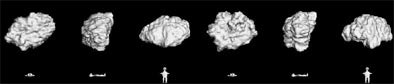

"And you can evaluate the growth rates in different parts; the solid and non-solid components (of the nodule) can be evaluated separately," he said. "So different aspects of this, different protocols, different workups, amounts of time between scans, it's going to be different for the different subtexts of abnormalities that we find."

![]() |

| Volumetric analysis of nodule size shows a doubling rate of greater than 750 days. |